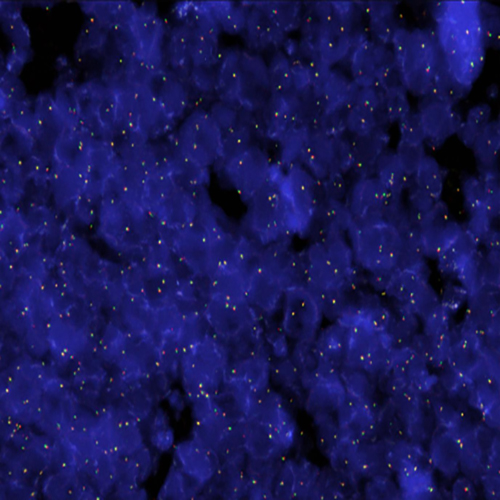

Hybridization of RET break probe to a tissue section showing abarrant pattern (1RG1R1G).

Pericentric inversion of chromosome 10 involving the RET (ret proto-oncogene) gene at chromosome 10q11 is known to increase expression of the RET gene by fusion with KIF5B (10p11). Translocations with other fusion partners have also been described. Elevated expression of RET is observed in non-small cell lung cancer (NSCLC), in which the function of tyrosine kinase-based therapeutics is based on the inhibition of such fusion proteins. Translocations involving RET have also been described in thyroid carcinomas. The RET (10q11) Break probe is optimized to detect translocations involving the RET gene region at 10q11.